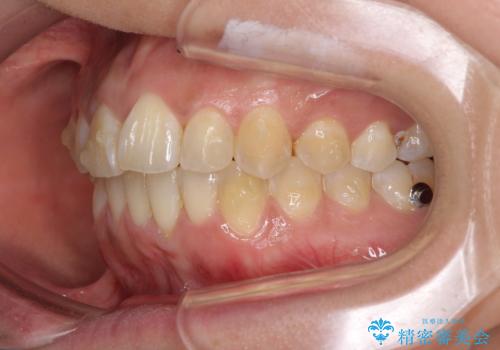

インビザラインによる狭窄歯列の拡大矯正

- 前歯のデコボコを治したいとのことで来院された患者様です。

上下顎ともに歯列全体の後方移動と側方拡大、IPR(歯と歯の間を削る)によってデコボコが解消するように設計し、インビザラインにより治療を行うこととしました。

後方移動に際し、上下の親知らずは4本とも抜歯することとしました。

治療途中で関西に転勤となってしまったため、東京に出張で来るタイミングに合わせて治療を進めることになりました。そのため、治療期間が長くなってしまいましたが、無事に仕上げることができました。